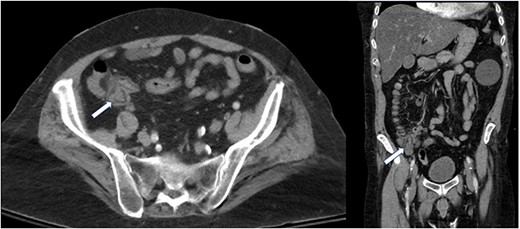

A computed tomography of the abdomen and pelvis (CT A/P) revealed a lobulated 2.4 × 2 cm mass at the cecal base without ascites or obvious metastatic disease (Fig. 1).

Absence of a cecal mass on colonoscopy, patent appendiceal orifice.